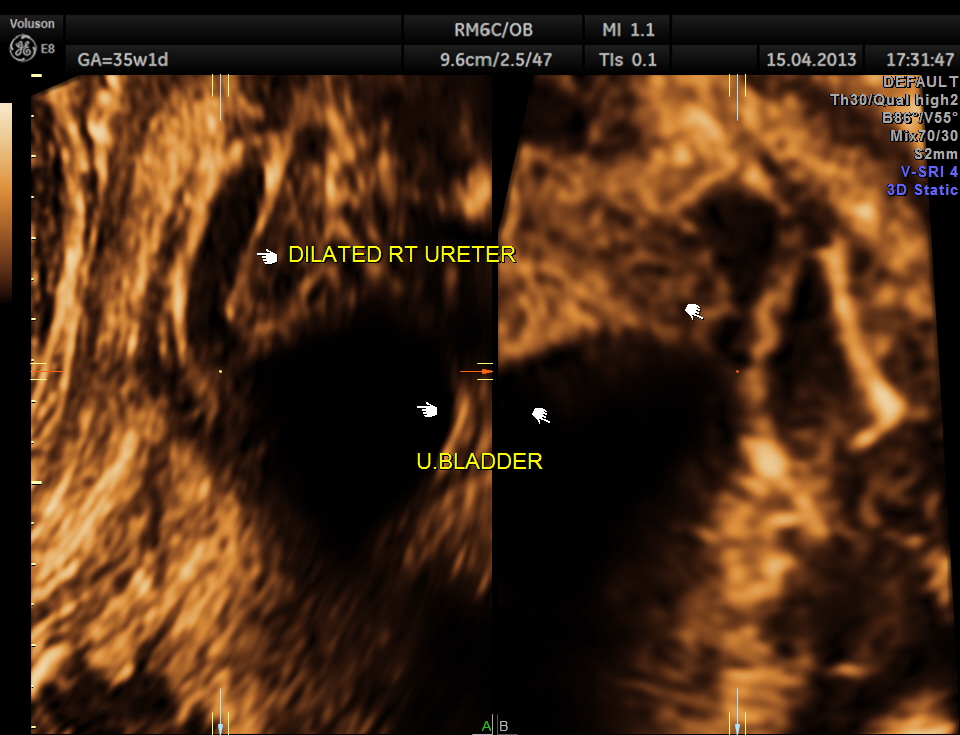

3 d reconstruction shows an echogenic tissue at the junction of ureter and bladder.

rendered image of the same